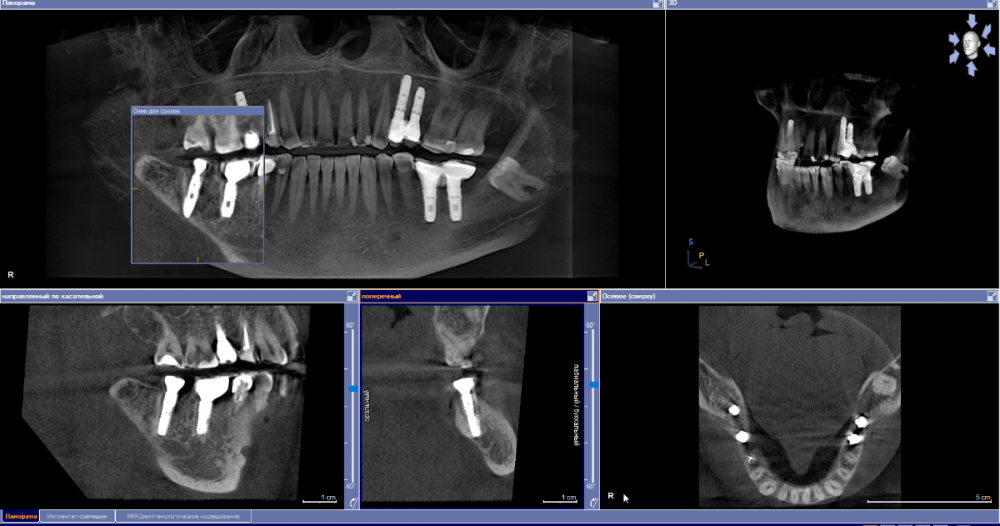

se77777 Опубликовано 5 апреля, 2023 Автор Поделиться Опубликовано 5 апреля, 2023 Спасибо. Ссылка на комментарий

red_butler Опубликовано 5 апреля, 2023 Поделиться Опубликовано 5 апреля, 2023 по Кт все нормально, нужно смотреть очно 1 Ссылка на комментарий

IvanK Опубликовано 6 апреля, 2023 Поделиться Опубликовано 6 апреля, 2023 Здравствуйте Покажитесь Вашему врачу Ссылка на комментарий